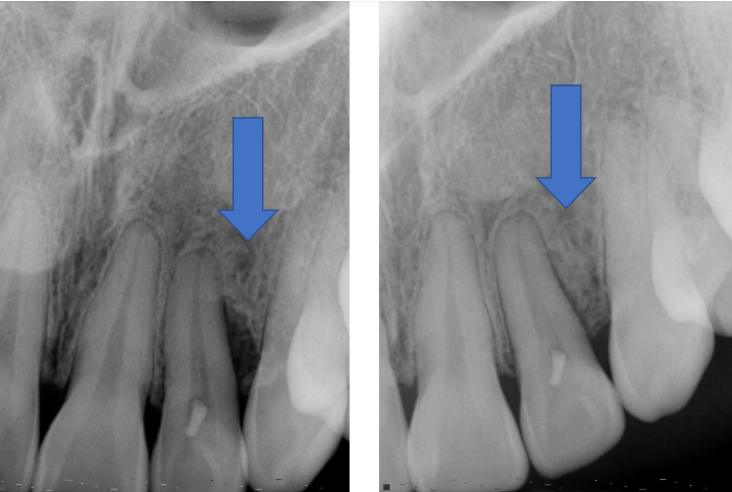

Before & After

Case by Dr. French